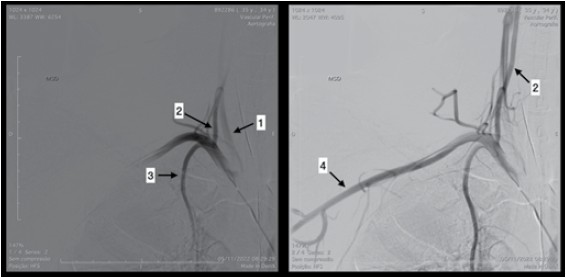

Observe a figura.

Com base na anatomia angiográfica apresentada na figura, assinale a alternativa correta.